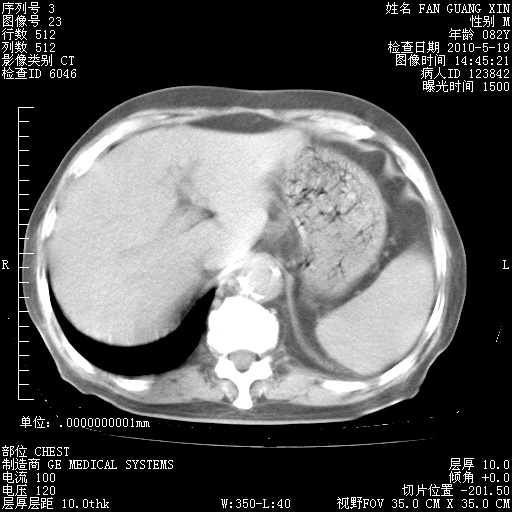

还需要哪些辅助检查?我们医院排除真菌感染没有任何检验方法,胸片好像能够排除肺部真菌感染。

补充:ENA化验全部阴性。免疫五项(IgG、IgA、IgM、C3、C4)只有C4略高。